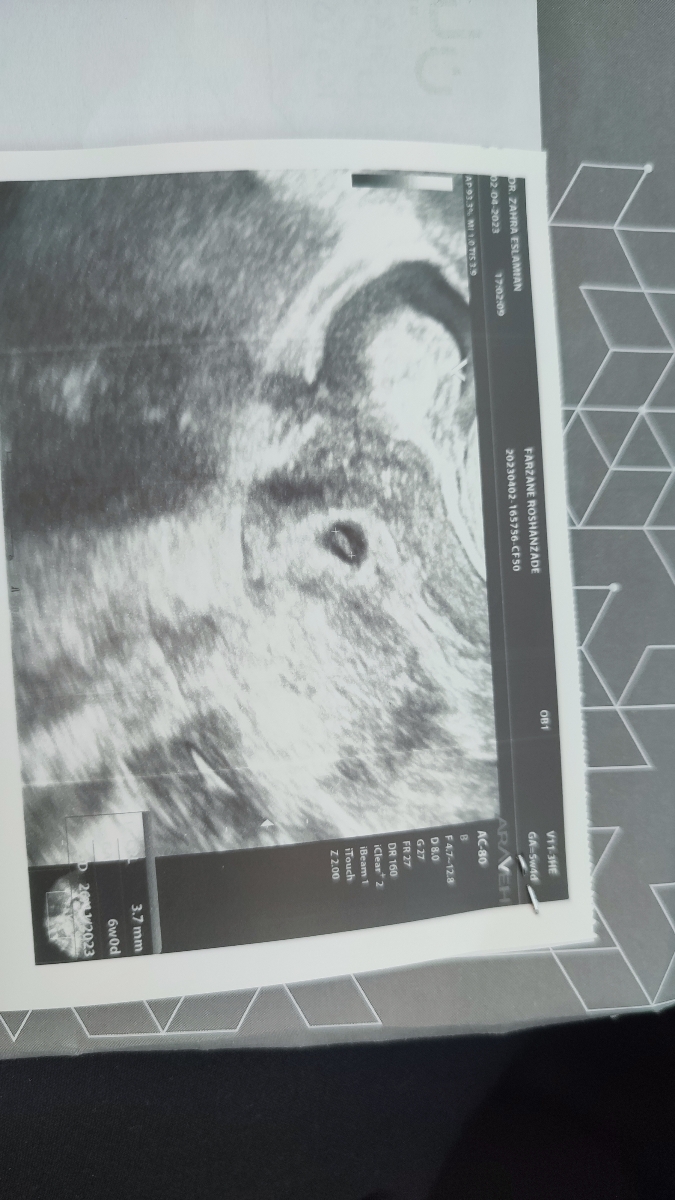

سلام خانم دکتر خوبید وقت بخیر

Farzan FR

0

بسلامتی مبارکه

صدای قلبش میشنوی

به به مبارکتان باشد جنین هم تشکیل شده دیگر کاری لازم نیست استراحت کنید آزمایشات ابتدایی بارداری را اول هفته بعد انجام داده و دو هغته دیگر سونوگرافی قلب بدهید 🌸🩷🌸